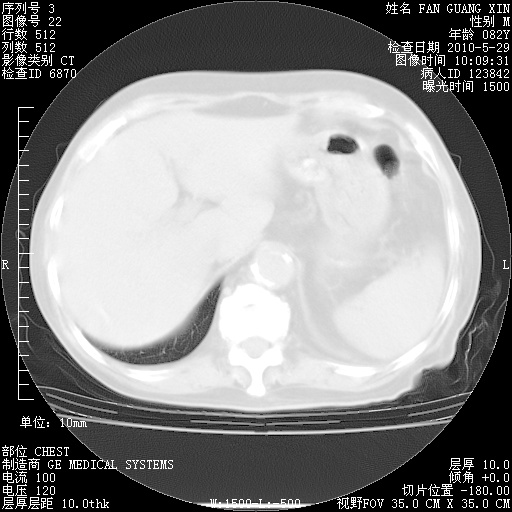

再治疗10天后的肺部CT 纵膈窗

阅读此次胸部CT,肺间质渗出性改变较入院时有吸收。目前从体温、白细胞、中性分叶明显增高,肯定存在细菌感染(发生医院感染哦,若无消化道及泌尿系统等感染的依据,肺部感染可能大)。若你院头孢哌酮舒巴坦钠耐药率较高,同意你的方案,若48小时体温仍高,可考虑使用碳青霉稀类抗菌药物,同时可予超声雾化、注意滴数时加大液体量。白蛋白33.30g/L较低哦,需加强营养等支持治疗。